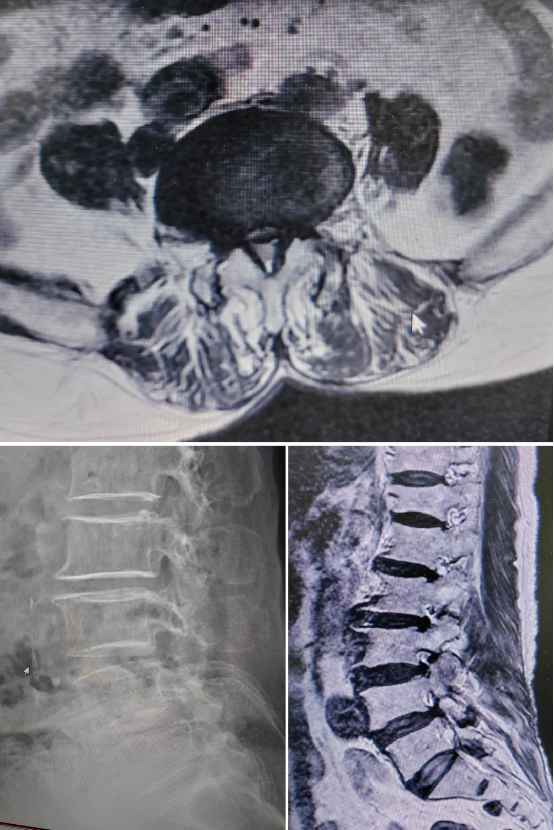

Patient: 77 years old, female

Preoperative Diagnosis: Lumbar spinal stenosis, lumbar instability

Surgical Plan: Robot-assisted MIS-TLIF surgery, with decompression first followed by screw placement.

During the procedure, Perlove Medical's 3D C-armperformed a 3D scan of the lumbar spine., and the 3D images were then imported into the robotic work system. The surgeon used the system's software to observe the patient's lumbar anatomy (intervertebral disc height, vertebral body size) and identified the diseased segment (L4-L5). A comprehensive surgical plan was then developed, defining the optimal trajectory for screw placement (including angle, depth, and diameter) and the optimal size and position for the interbody cage, ensuring the plan was customized to the patient's individual anatomy.